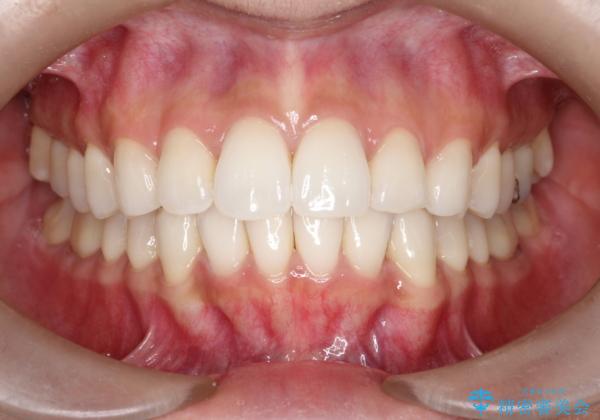

歯と歯の間にヤスリを入れてわずかに歯を削ることでスペースを確保する処置をIPRと呼びます。

当院では拡大鏡を用いて丁寧に処置することで歯冠形態を損なわずに行うことができます。